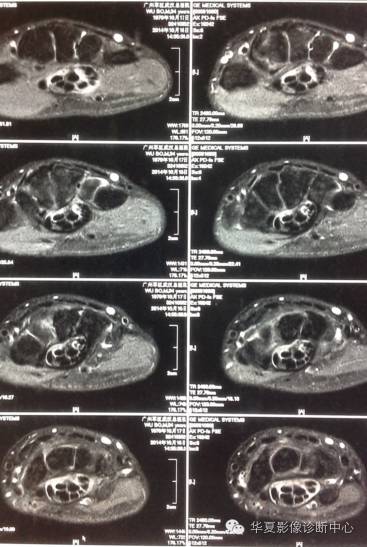

MRI影像表现:1.掌侧环状韧带膨出;2.正中神经受压水肿,体积大,T2高信号;3.伴发表现:腱鞘炎、滑膜囊肿等。

CT影像表现:掌侧环状韧带、正中神经体积增大,可见混杂密度,以中等低密度为主,部分可见有包裹征,界面不清。